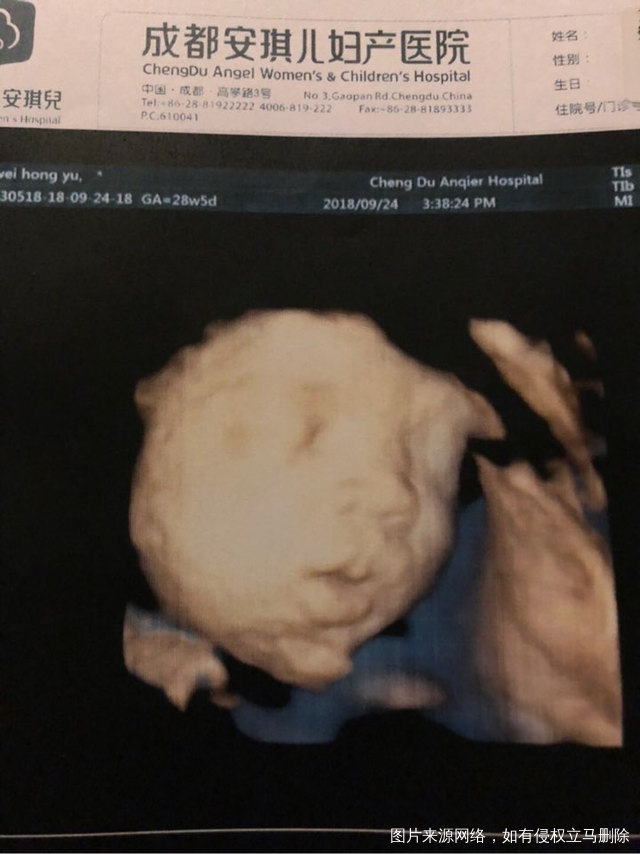

孕28+5。双顶径8.3

我已经要哭晕在厕所了,宝宝头怎么会这么大啊?股骨才5.7。羊水目前18.6,还是偏高一些。